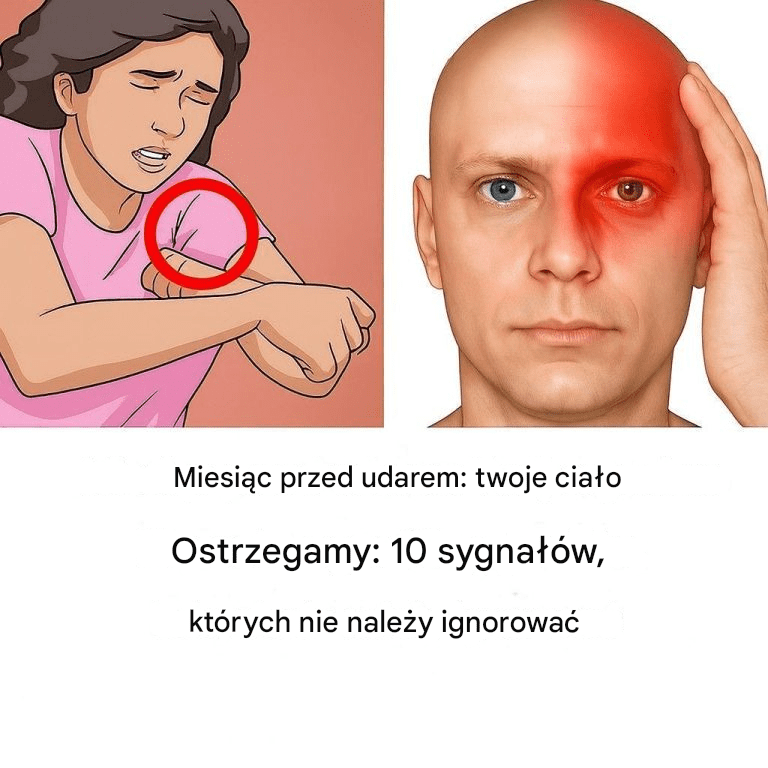

Na miesiąc przed udarem twoje ciało ostrzega: 10 sygnałów, że nie powinieneś ignorować

Widzenie tunelu: Utrata widzenia obwodowego może być opodatkowana. Utrata koordynacji: Natychmiast skontaktować się z lekarzem, jeśli Twoje ruchy staną się nieskoordynowane. Problemy z mową:…